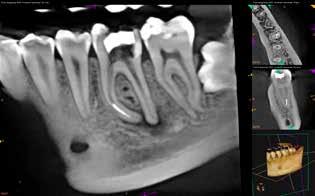

A páciens a jobb alsó első nagyőrlőfogából kiinduló közepes erősségű fájdalom miatt kereste fel a rendelőnket. Periapikális röntgen és CBCT-felvétel is készült. Mindkét felvétel a mesiobukkális gyökércsúcs körül található radiolucens elváltozás jelenlétét igazolta. Ezenfelül a mesialis gyökérben két betört eszközdarab is észlelhető volt. Az egyik a középső gyökéri harmadban a gyökérgörbület előtt volt megtalálható, a másik pedig kicsivel a gyökérgörbület után (12–13. ábra).

12. ábra: A kiindulási CBCT-felvételen jól látható a periapikális felritkulás. – 13. ábra: A kiindulási röntgenfelvételen látható a két betört eszközdarab.

26. ábra: A kiindulási CBCT-felvételen két egymástól jól elkülöníthető periapikális lézió látható. – 27. ábra: A kiindulási röntgenfelvételen jól láthatóak a betört eszközök.

Hat hónap és 12 hónap múlva kontroll CBCT-felvétel készült (24–25. ábra). A felvételeken nem láttuk periapicalis gyulladás jeleit, valamint a páciens a gyökértömés elkészítése óta teljesen panaszmentes volt.